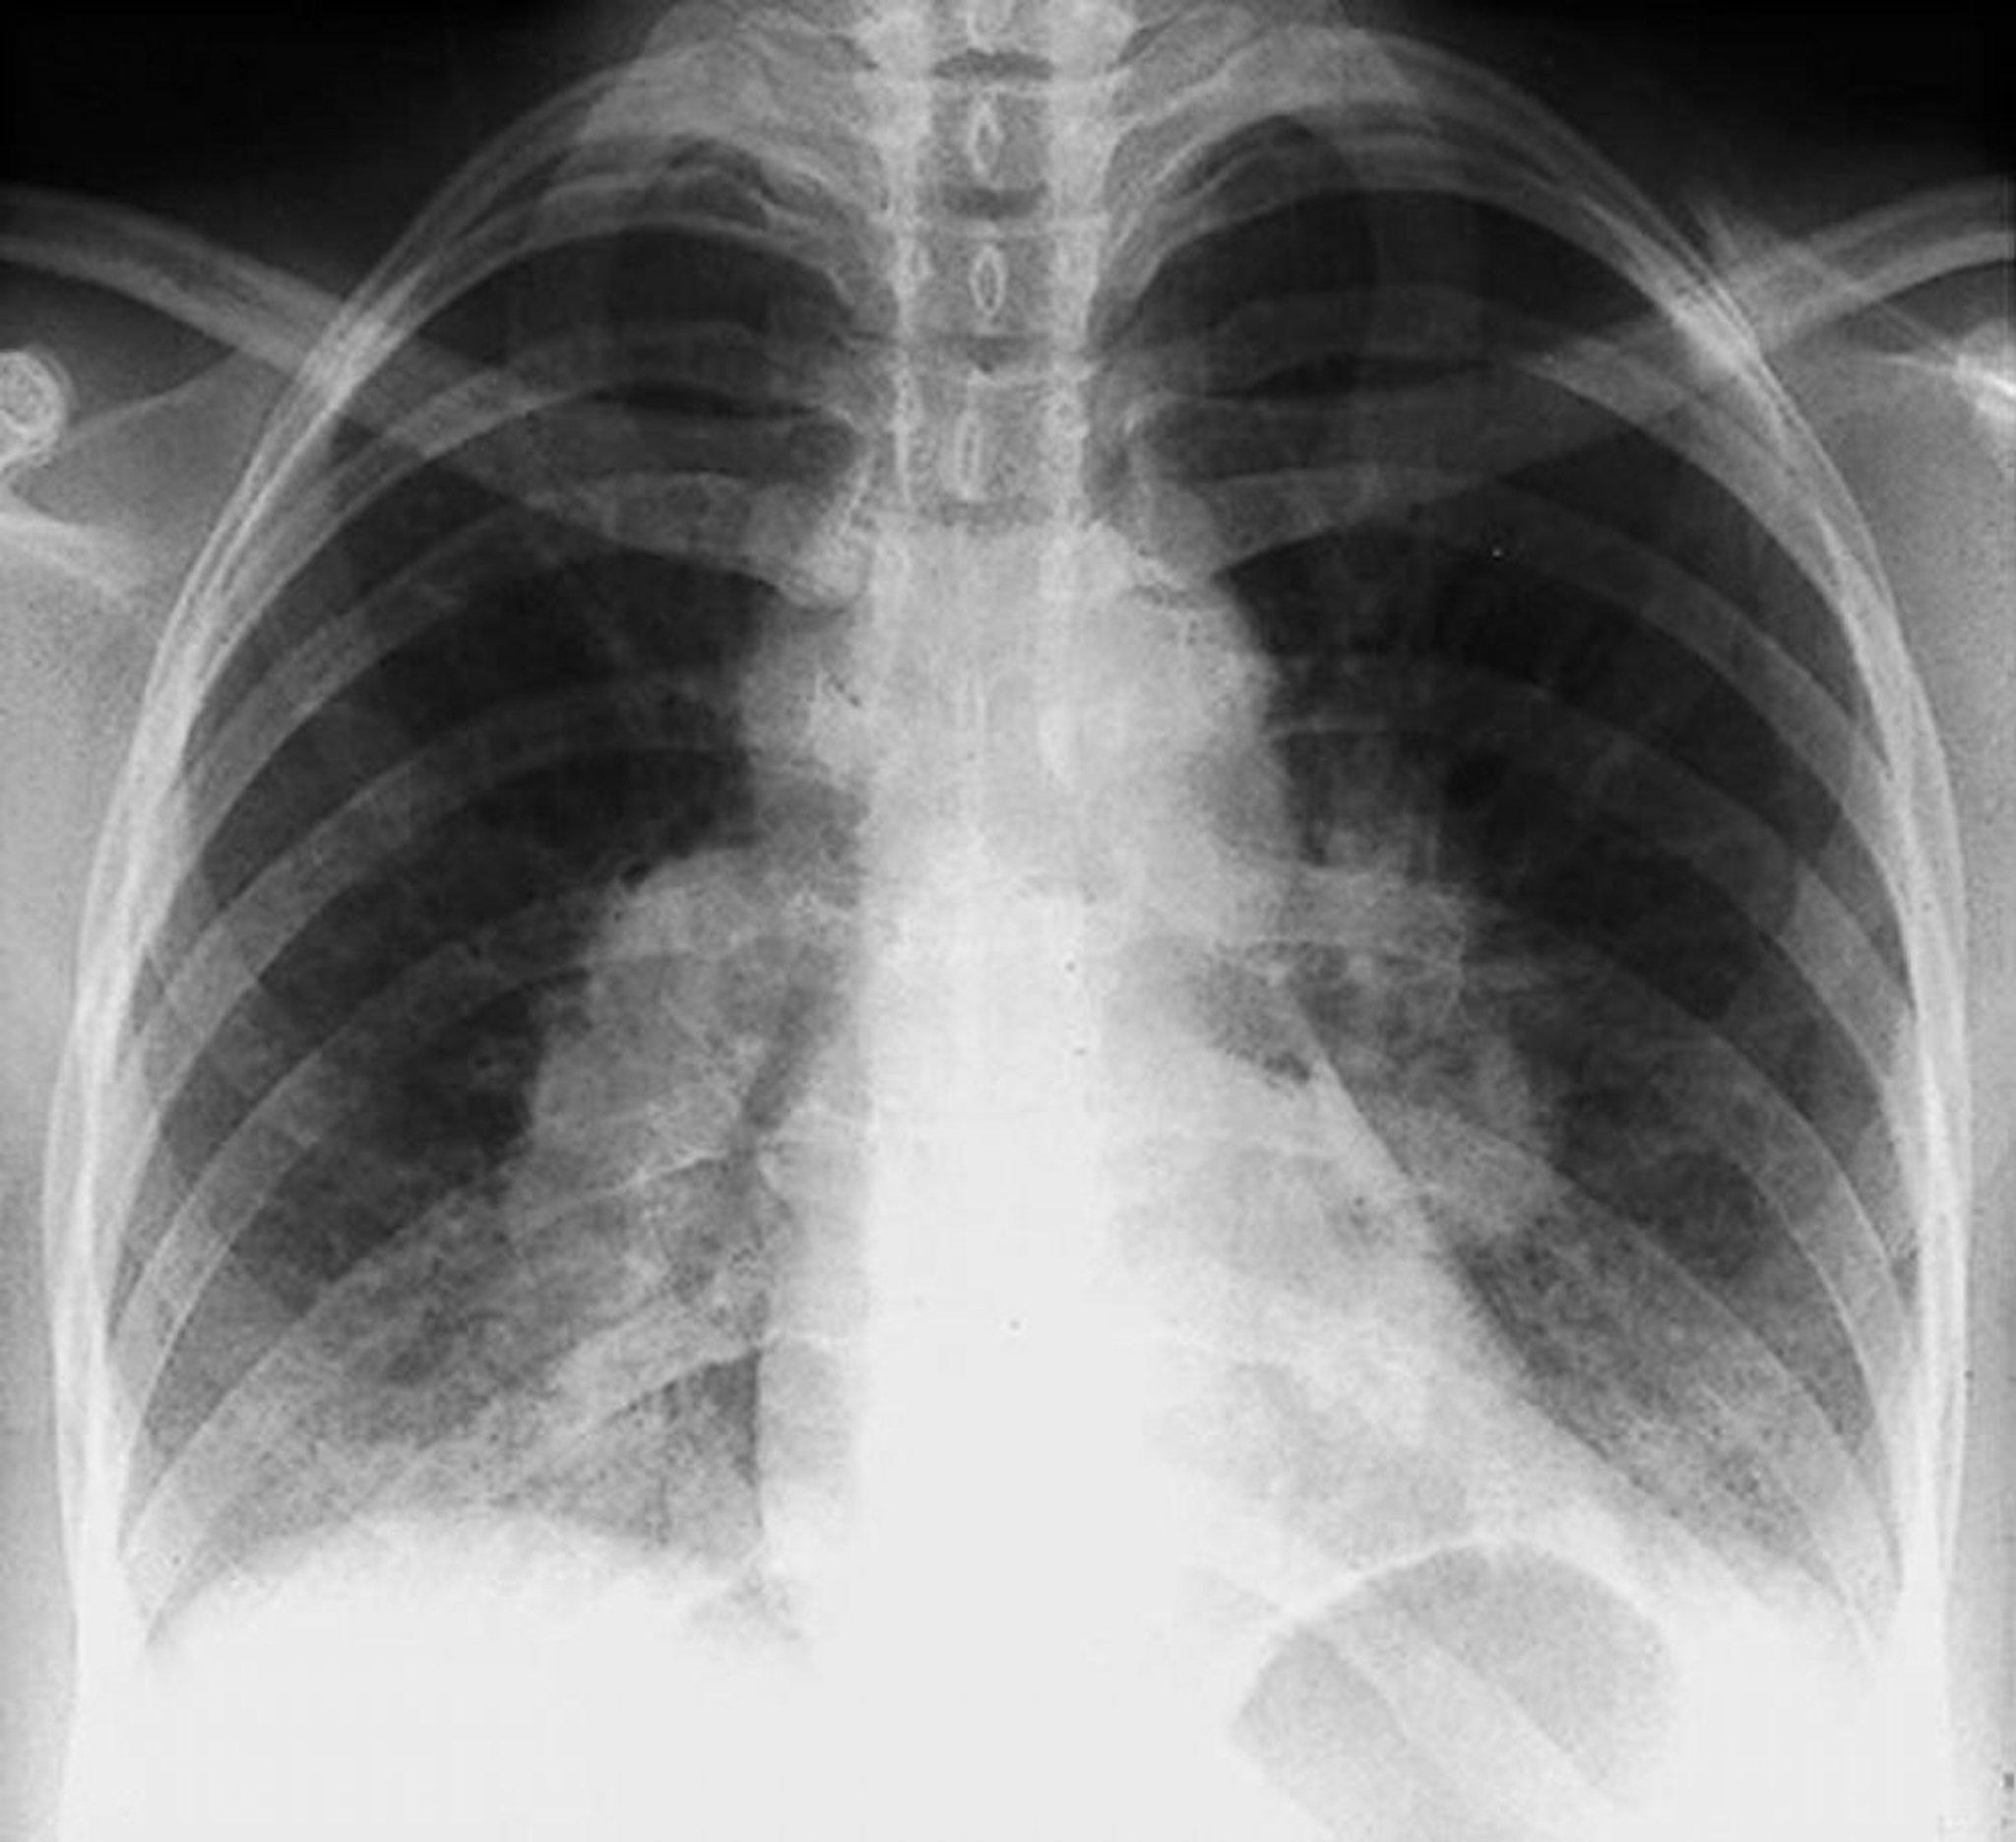

Sarcoidosi (stadio I)

Adenopatia ilare bilaterale nella sarcoidosi di stadio I.

By permission of the publisher. Da Tanoue L, Elias J. In Bone's Atlas of Pulmonary and Critical Care Medicine. Edited by J Crapo. Philadelphia, Current Medicine, 2005.